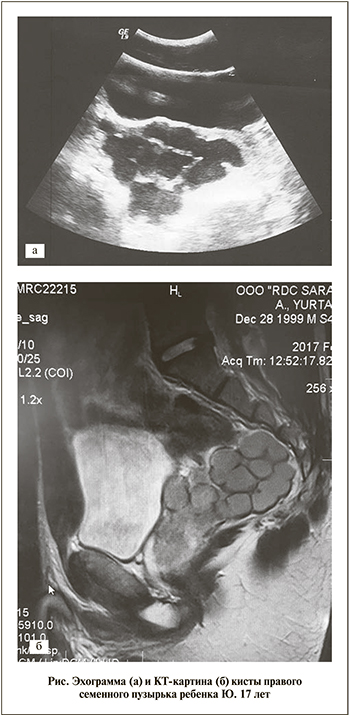

Данные УЗИ органов мочевой и половой системы от 27.02.2017. Правая почка на обычном месте не определяется. Левая почка размером 140×65 мм расположена на обычном месте, контуры ровные, толщина паренхимы – 19 мм. Чашечно-лоханочная система незначительно расширена. Мочевой пузырь наполнен, объем его составляет 400 мл, стенки ровные. Предстательная железа: размер – 41×29×35 мм, контуры ровные, структура однородная. Отмечается расширение семенного пузырька справа, который визуализируется в виде кистозного образования размером 85×66×90 мм с множественными перегородками. Заключение: киста правого семенного пузырька, агенезия правой почки.

23.02.2017 выполнена серия МРТ-исследований органов малого таза (см. рисунок). Слепая и прямая кишка не изменена. Прямая кишка оттеснена влево. Предстательная железа размером 3,2×2,5×3,8 см, контуры четкие и ровные. Левый семенной пузырек не увеличен. В проекции правого семенного пузырька определяется объемное поликистозное образование неправильной формы с четкими контурами размером 8,3×6,6×7,6 см, деформирующее стенку мочевого пузыря, предстательную железу, оттесняющее прямую кишку влево. Заключение: киста правого семенного пузырька.

Per rectum: ампула прямой кишки пуста, справа от предстательной железы определяется объемное болезненное образование размером 7,5×7×7,6 см. Предоперационный диагноз: инфицированная киста правого семенного пузырька, агенезия правой почки.